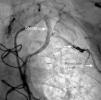

The coils were attached to a delivery wire and were released in the appropriate position. During the procedure, a dissection was detected in the proximal region of the LIMA and two biolimus and bioabsorbable polymer stents (Biomatrix 3 mm × 24 mm and 3 mm × 28 mm distal and proximal, juxtaposed) were implanted, covering the entire dissected segment. Control angiography at the end of the procedure showed the side branch still patent but with compromised flow (Figure 2)